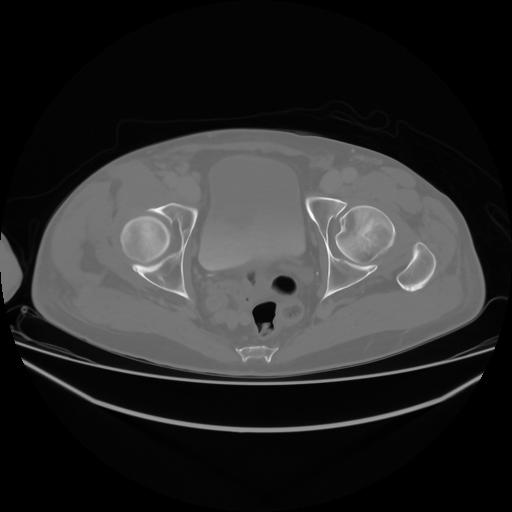

4 CUERPO,CE,Axial,3.0,CUERPO,,